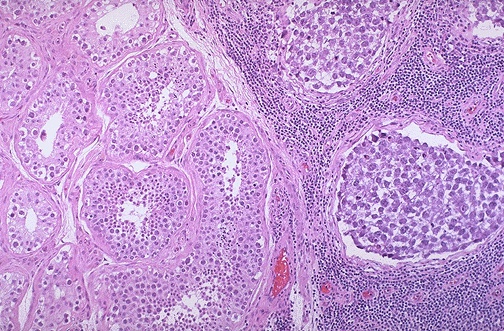

Normal testis appears at the left, and seminoma is present at the right. Note the difference in size and staining quality of the neoplastic nests of cells compared to normal germ cells. Note the lymphoid stroma between the nests of seminoma.